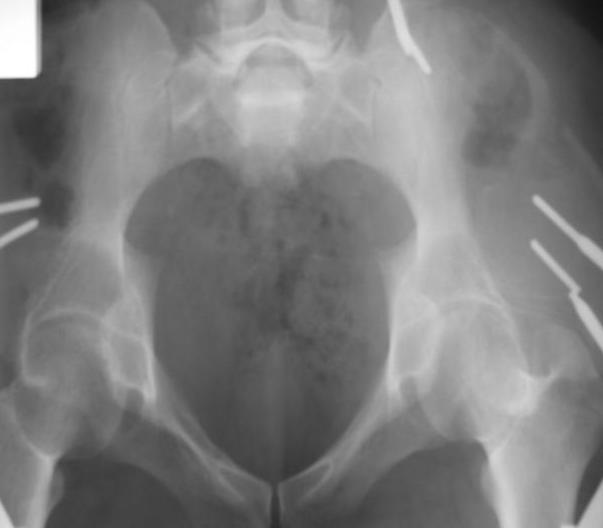

Поступил пациент после кататравмы (упал с высоты 4м). После обследования установлен Ds: Сочетанная травма. ЗТГК перелом 5-6 ребер справа. Ушиб левого леогкого. Оскольчатый перелом крыла подвздошной кости слева, со смещением. в экстренном порядке выполнена операция о/синтез таза стержневым аппаратом. Снимки прилагаются. Пациент со 2-го дня стал ходить без костылей. Из анамнеза жизни у пациента имеется гепатит В и С, с 1998г. употребляет наркотики (героин 1г в день нормальная доза). На контрольных снимках таза в аппарате смещение отломков сохраняется, да еще и стержни сломались. Подскажите ув.коллеги, как поступить в данной ситуации: оставить все как есть или добиваться репозиции в аппарате, или планировать на открытую репозицию. На сегодняшний день пациент стабилен, по анализам компенсирован. Принимает героин по другому справиться не может. С ув. Андрей